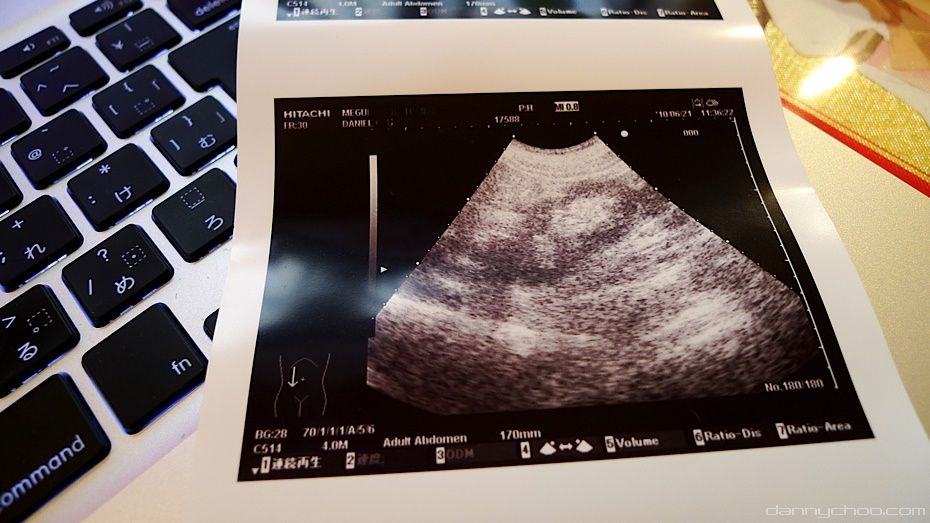

Then its time to scan the stomach to see if everything is in order.

Was given this scan of my stomach. Looks like I'm expecting.